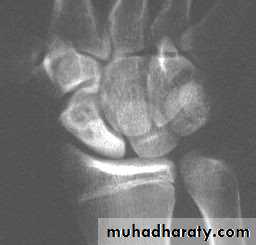

Complications

1-Avascular necrosis The proximal fragment may die,especially with proximal pole fractures, and then at 2–3 months it appears dense on x-ray.2-Non-union By 3 months it may be obvious that the fracture will not unite with sclerosis and cavitation. Bone grafting with compression screw should be attempted, especially in the younger, more vigorous type of patient, because this probably reduces the chance of later, symptomatic osteoarthritis.

3-Osteoarthritis: Non-union or avascular necrosis may lead to secondary osteoarthritis of the wrist.

The treatment either by wrist arthrodesis or proximal raw carpectomy.